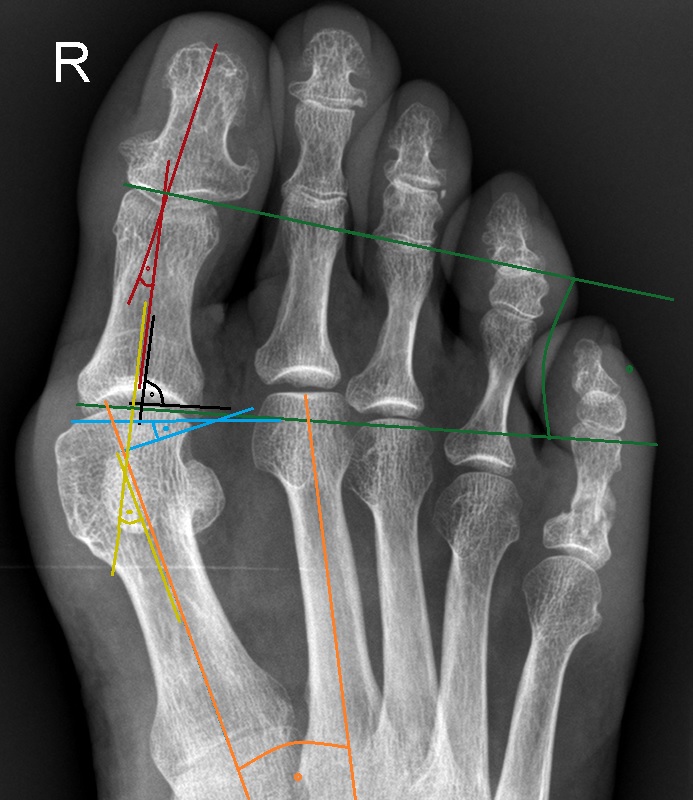

Die Akin-Osteotomie erfolgt in mindestens 50% begleitend zu metatarsalen Osteotomien im Rahmen der Korrektur einer Hallux valgus Deformität 12. Diese gehören zu den am häufigsten durchgeführten orthopädischen Eingriffen. Eine präzise Planung der notwendigen Korrektur unter Berücksichtigung aller Komponenten ist daher unabkömmlich. Dabei sollte eine Valgus-Deformität der Grundphalanx mitbehandelt werden, da diese die Entwicklung eines Rezidivs begünstigt. Die valgische Deformität der Grundphalanx mit veränderten Gelenksflächenwinkeln wird als Hallux valgus interphalangeus bezeichnet (Abb. 1). Dabei können verschiedene Winkel zur Definition der Fehlstellung angegeben werden (Abb. 2) 34. Bei der Beurteilung des Hallux valgus interphalangeus im Rahmen einer Hallux valgus Deformität ist zu beachten, daß häufig eine Hyperpronation der Grundphalanx besteht. Durch diese Malrotation werden die eigentlichen pathoanatomischen Winkel "verprojiziert". Am Röntgenbild erscheinen diese projizierten kleiner als die reellen Winkel. Somit sollte intraoperativ nach einer metatarsalen Osteotomie überprüft werden, ob eine Restfehlstellung im Sinne eines Hallus valgus interphalangeus besteht, da das präoperative Röntgenbild die Fehlstellung nicht immer exakt abbildet.

• Röntgenaufnahme des Fußes (unter Belastung) in dorsoplantarem und seitlichen Strahlengang (Abb. 3) und präoperative Fotodokumentation.

• Beurteilung des proximalen Gelenkflächenwinkels der Grundphalanx (Proximal Phalangeal Articular Angle, PPAA) des Hallux valgus interphalangeuswinkels (Hallux interphalangeus Angle, HIA) sowie des proximalen zum distalen Gelenksflächenwinkel (Proximal to Distal Phalangeal Articular Angle, PDPAA) 6789 (Abb. 2).

• Bei Hallux valgus Problematik: Bestimmung des ersten Intermetatarsalwinkels (IMA), des Hallux valgus Winkels (HVA), des distalen metatarsalen Gelenskflächenwinkels (DMAA) 68.